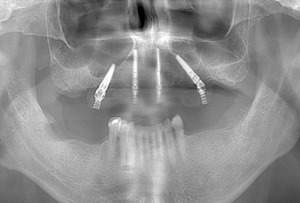

インプラント2本の予定ですので、インプラント同士をほぼ並行に埋入する計画を立てます。神経にインプラントが当たりますと、麻痺が起きたり出血の原因になりますので、

シュミレーション上でもしっかり神経とは距離をおきます。

【担当医師所見】

歯ぐきを切ってインプラントを埋入しました。埋入後は歯ぐきを縫って終わります。

この状態で4ヶ月待ちインプラントと骨の生着を待ちます。